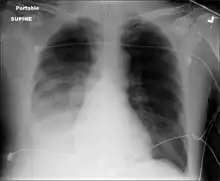

Pneumococcal antigen (cell wall C polysaccharide) may be detected in various body fluids. Older detection kits, based on latex agglutination, added little value above Gram staining and were occasionally false-positive. Better results are achieved with rapid immunochromatography, which has a sensitivity (identifies the cause) of 70–80% and >90% specificity (when positive identifies the actual cause) in pneumococcal infections. The test was initially validated on urine samples but has been applied successfully to other body fluids.[28] Chest X-rays can also be conducted to confirm inflammation though are not specific to the causative agent.[29][13]

Chest X-ray pneumonia

CT pneumonia